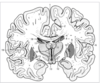

Key gyri on medial view of frontal lobe

Superior frontal gyrus

Paracentral lobule

Cingulate gyrus

Key sulci on medial surface of frontal lobe

Cingulate sulcus

Key gyri on orbital view of frontal lobe

Gyrus rectus

Medial orbital gyrus

Anterior orbital gyrus

Posterior orbital gyrus

Lateral orbital gyrus

Key sulci on orbital surface of frontal lobe

Olfactory sulcus

Orbital sulcus